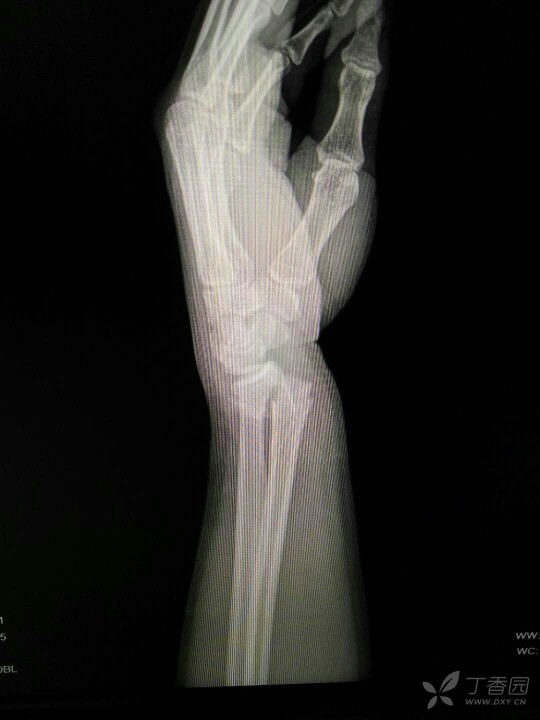

典型的腕骨脱位片子

目前诊断:左腕经桡骨茎突月骨周围脱位-骨折可能伴三角骨或月骨脱位